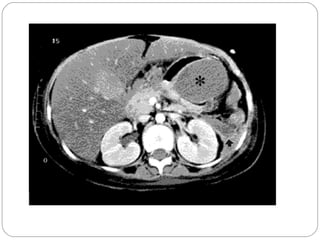

Quiste Pancreático

• Pseudoquiste: formación de densidad líquida caracterizada por la

existencia de una pared de tejido fibroso o granulatorio que

aparece no antes de las 4 semanas desde el inico del cuadro.

• Ecografia: Puede revelar un páncreas tumefacto,

edematoso, acumulaciones peripancreáticas de

líquido o seudoquistes.

• Tomografía axial computadorizada con contraste:

Puede apreciarse la viabilidad del páncreas en las

zonas en la cual realza el contraste.